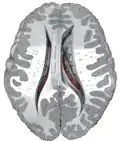

Le noyau caudé présente une extrémité antérieure renflée (la tête), un corps effilé et de volume décroissant et une queue.

La tête du noyau caudé est reliée au putamen par des ponts putamino-caudés traversant le bras antérieur de la capsule interne.

Il s'enroule d'avant en arrière autour du thalamus où il forme la paroi latérale des ventricules latéraux, s'incurve au niveau du pulvinar, sous le splenium du corps calleux, et se réfléchit d'arrière en avant au sein du lobe temporal, au-dessus de la corne temporale du ventricule latéral, pour se terminer en arrière de l'amygdale cérébrale.